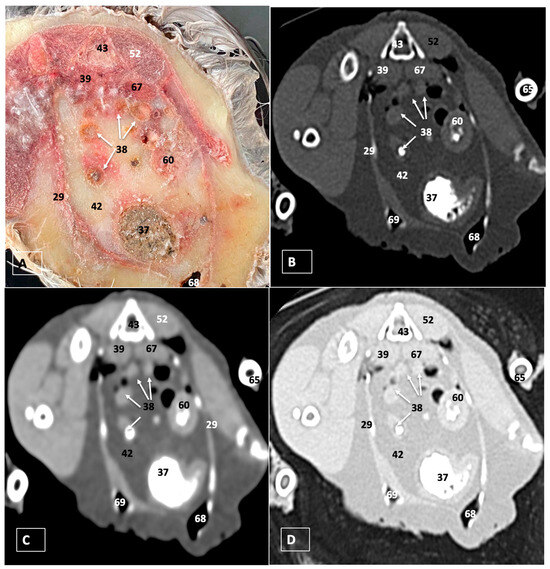

3. Results

3.1. Anatomical Dissections and Cross-Sections

3.2. Computed Tomography Images